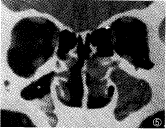

图2 双侧漏斗型副鼻窦炎。燕尾箭头 示筛漏斗混浊,长三角箭头示中鼻甲气房

本文所指的OSCO区是构成中鼻道周围的一组复杂解剖结构,包括中鼻甲、筛泡、半月裂、钩 突和筛漏斗,前组副鼻窦均引流开口于此。额窦经额前隐窝开口于中鼻道前上部;前中组筛 窦通过筛泡下部的数个小孔,经半月裂开口于中鼻道;而上颌窦则主要通过筛漏斗进入中鼻 道,有的另有副口与之相通。该区是呼吸气流的主通道,是炎症和息肉的始发和多发区 [2,3]。除病变外,该区的解剖变异,如中鼻甲气房(图2)、筛泡过大、Haller气房、 中隔弯曲等,也可导致开口狭窄或闭塞,使之引流不畅,反复感染,最后演变为前组慢性副 鼻窦炎[6]。